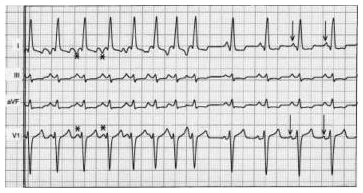

A figura representa um eletrocardiograma de um paciente com taquicardia atrial esquerda com ondas P negativas em D1 e av1, onde se observa: